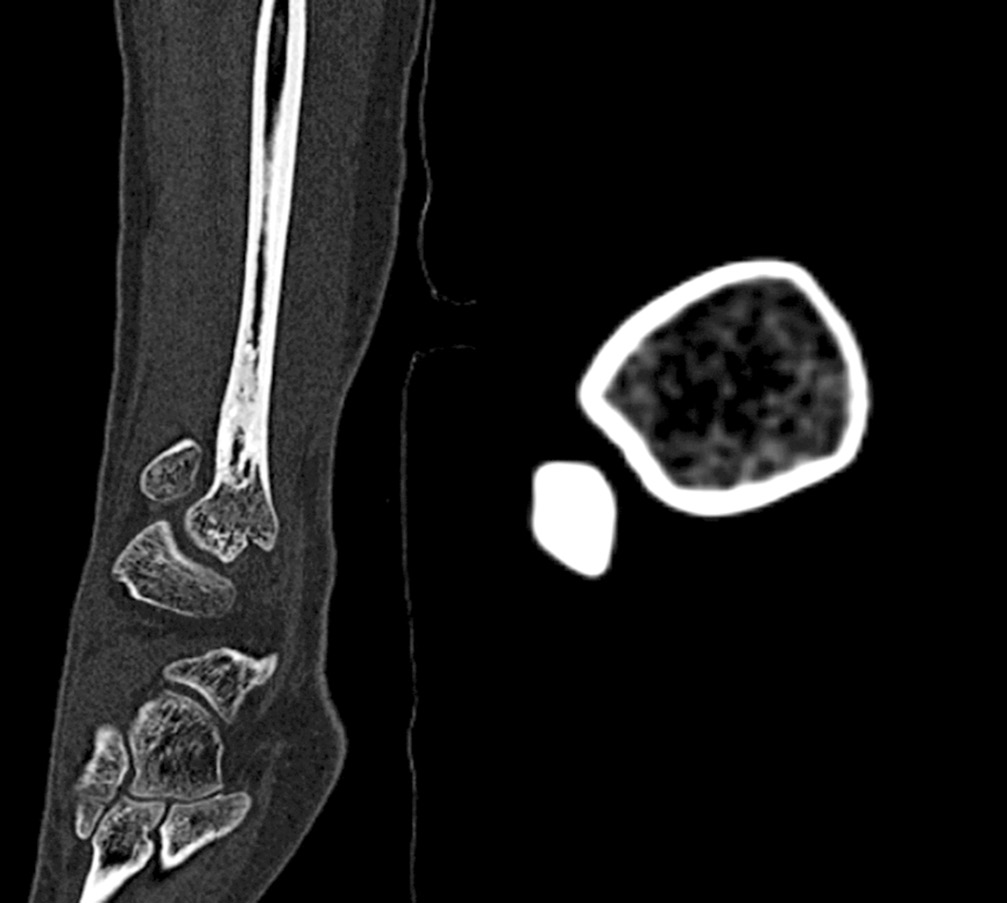

После получения травмы голеностопного сустава у 13-летней пациентки при рентгенологическом обследовании обнаружен очаг деструкции нижней трети правой малоберцовой кости овальной формы размером 1,9 × 0,8 см (30.11.2012) (рис. 1). Был рекомендован рентгенологический контроль через каждые 6 мес. Спустя год на снимке определялось увеличение размеров полости до 2,2 × 1,0 см. Пациентка жаловалась на непостоянный болевой синдром слабой выраженности (по визуальной аналоговой шкале (ВАШ) 2–3 балла), усиливающийся при физических нагрузках (по ВАШ до 5–6 баллов).

Рис. 1. Рентгенограмма. В проекции нижней трети правой малоберцовой кости кистозное образование овальной формы с четкими, ровными контурами, размером 1,9 × 0,8 см, кортикальный слой на уровне образования истончен